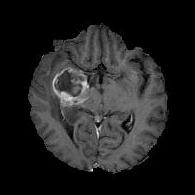

(a) (b) (c) (d)

Boundary Stream:

Fig. 2 demonstrates the output of each of the attention layers in our dedicated boundary stream. In essence, each attention layer progressively localizes the tumor and refines the boundaries. The first attention layer has learned rough estimate of the boundaries around the tumor and localized it, whereas the second and third layers have learned more fine-grained details of the edges and boundaries, refining the localization. Moreover, since our architecture leverages a dilated spatial pyramid pooling to merge the learned feature maps of the regular segmentation stream and the boundary stream, multiscale regional and boundary information have been preserved and fused properly, which has enabled our network to capture the small structural details of the tumor.